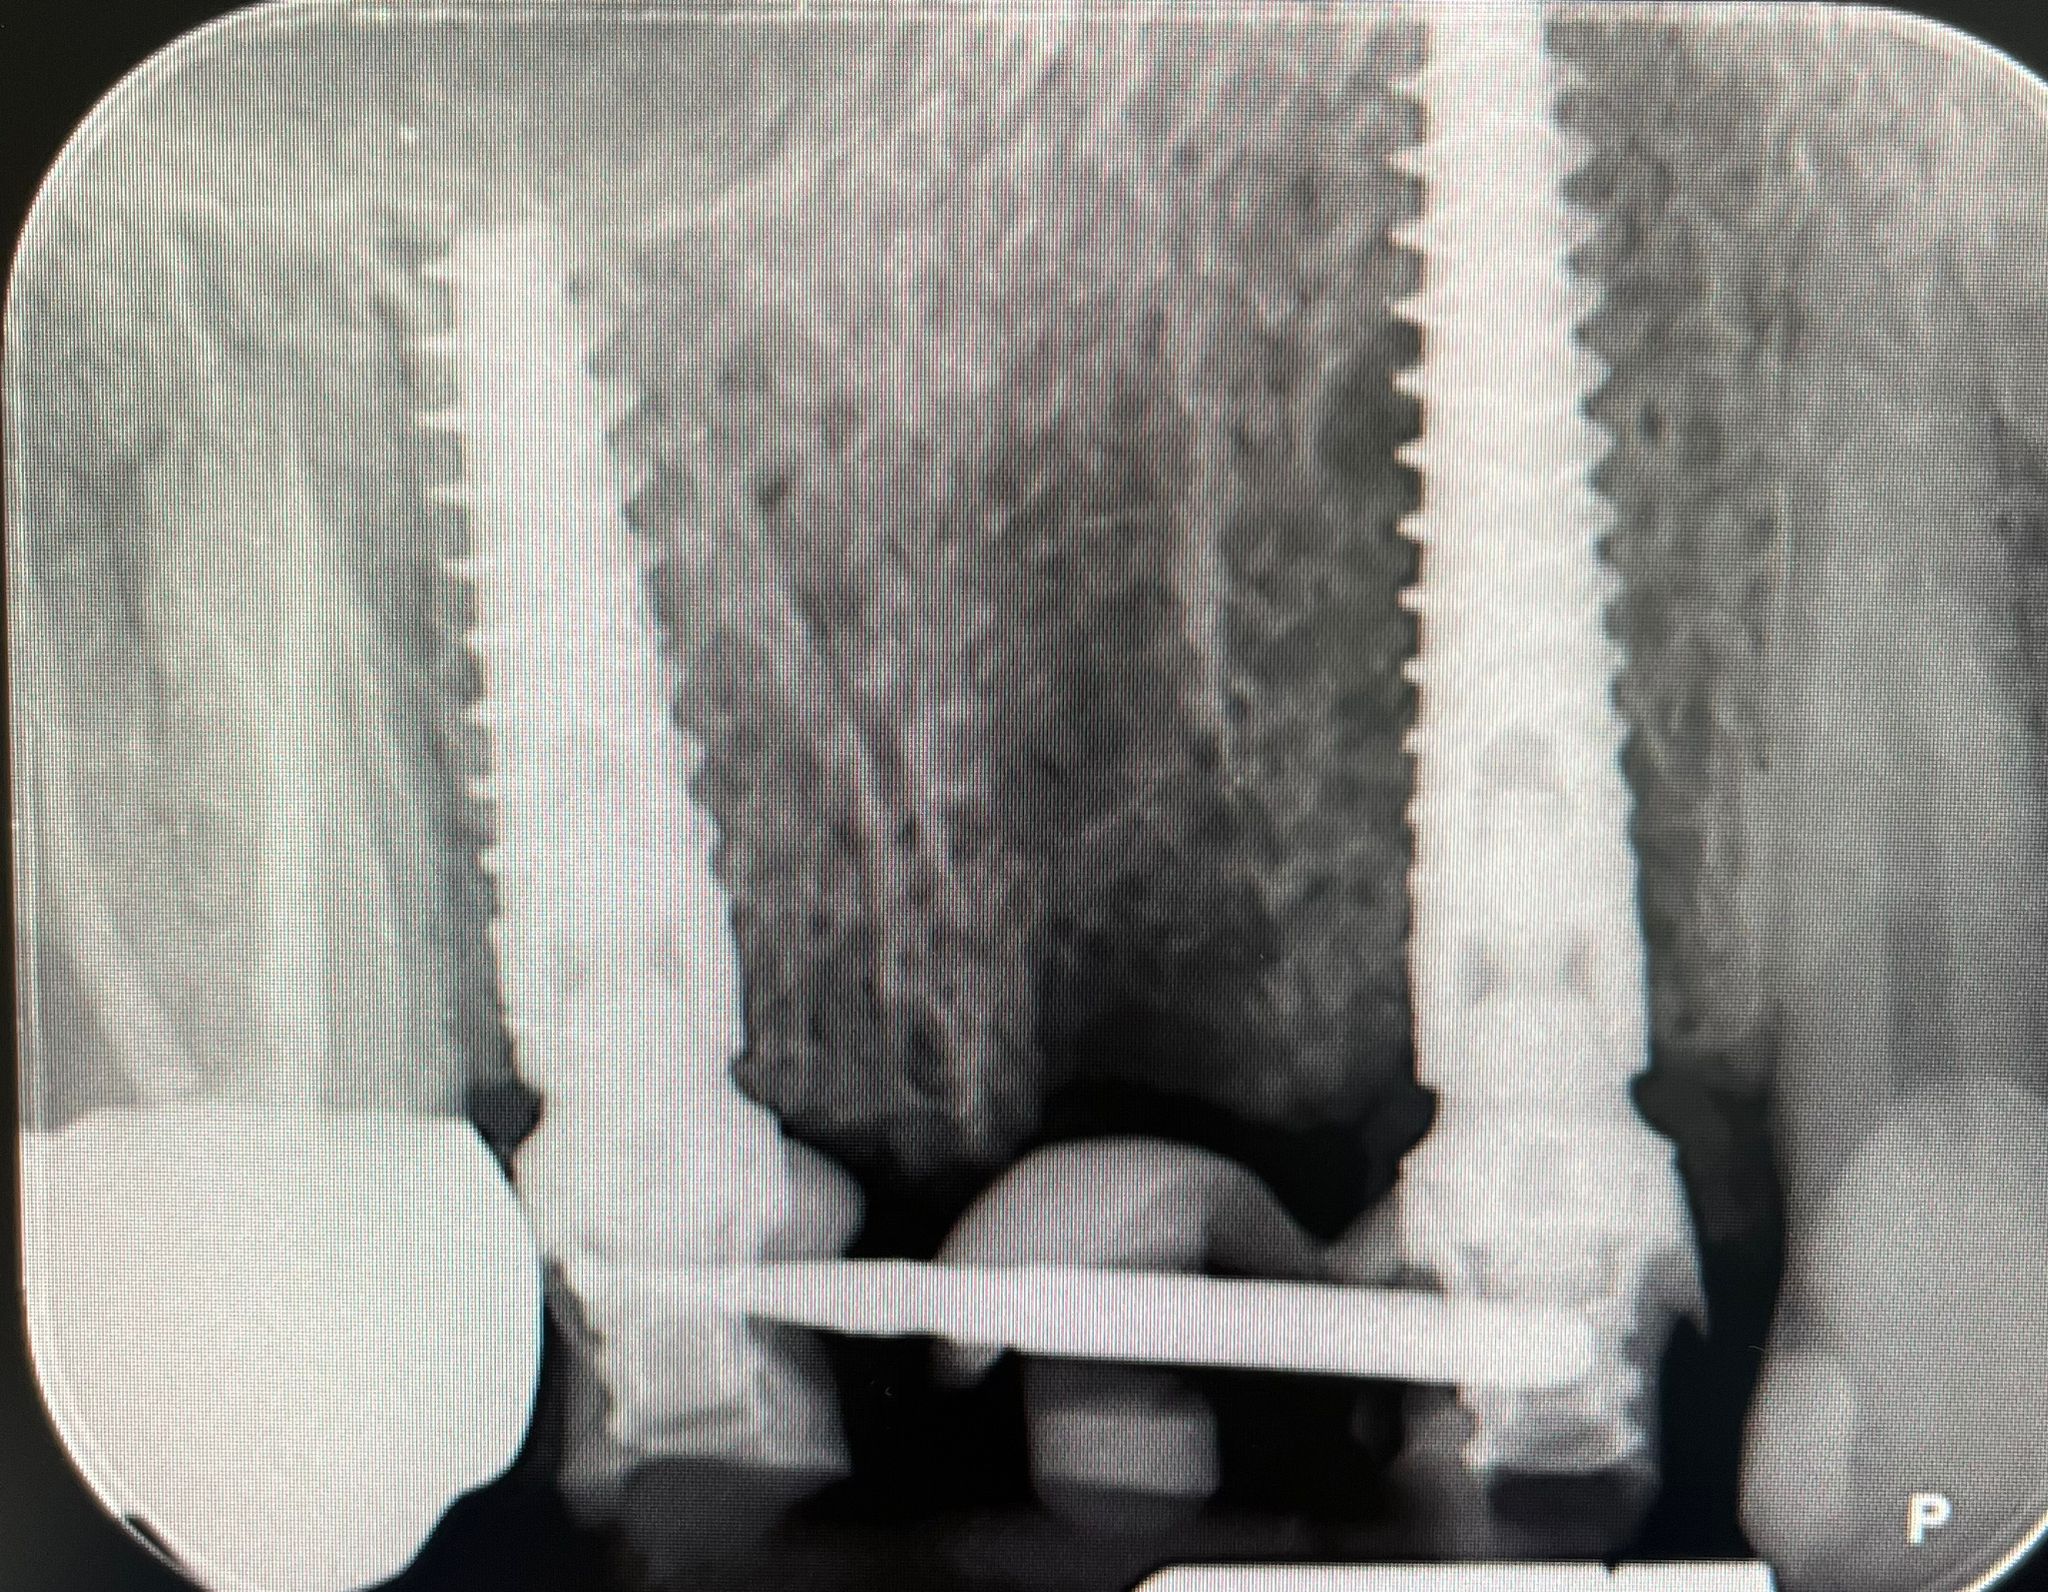

Presso lo Studio Dentistico Zambon siamo specializzati in trattamenti avanzati come il postestrattivo con carico immediato, un intervento innovativo che consente di sostituire i denti mancanti in modo rapido e sicuro, riducendo notevolmente il tempo di guarigione e il disagio per il paziente.

Grazie all’utilizzo della chirurgia guidata, siamo in grado di pianificare e realizzare impianti dentali con precisione, assicurando risultati eccellenti e duraturi.

Il trattamento postestrattivo con carico immediato è un protocollo che permette di inserire un impianto dentale subito dopo l’estrazione del dente naturale, evitando lunghi tempi di attesa tra l’estrazione e l’inserimento del nuovo dente. Questa soluzione si dimostra ideale per chi desidera ripristinare il sorriso e la funzionalità dei denti in tempi ridotti, evitando multiple sedute e massimizzando il comfort.

La chirurgia guidata è una tecnica avanzata che si avvale di tecnologie digitali per pianificare e simulare l’intervento in modo personalizzato. Con una scansione digitale 3D della bocca, il nostro team può posizionare gli impianti con estrema precisione, seguendo un percorso predefinito che riduce il margine d'errore. Questo approccio, unito al trattamento postestrattivo con carico immediato, offre diversi vantaggi: